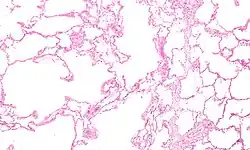

![]() | |

| Section of a lung showing centrilobular emphysema, with enlarged airspaces in the centre of a lobule usually caused by smoking and a major feature of COPD | |